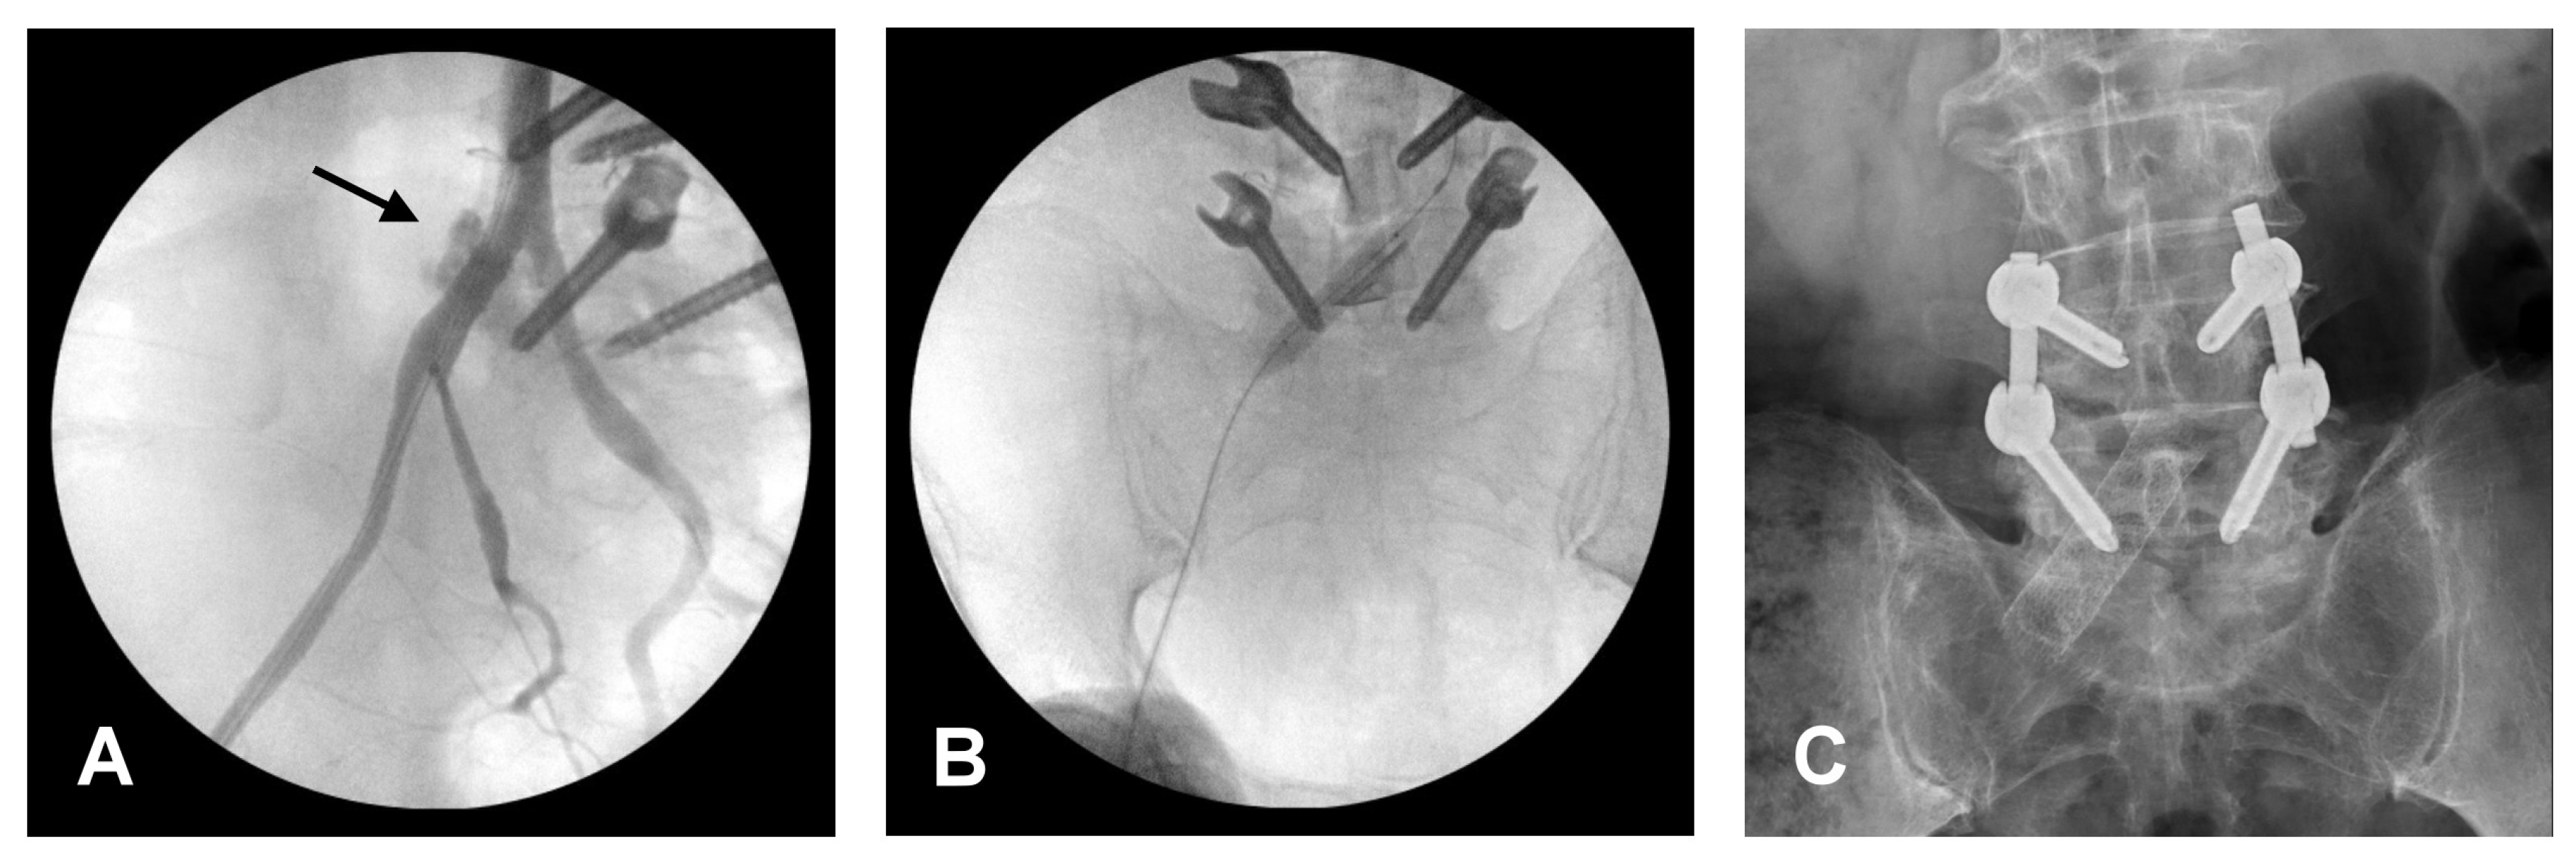

2. Illustrative Case